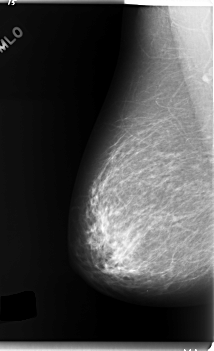

C_0124_1.RIGHT_MLO

RIGHT_CC LINES 5872 PIXELS_PER_LINE 3408 BITS_PER_PIXEL 12 RESOLUTION 50 NON_OVERLAY

RIGHT_MLO LINES 5952 PIXELS_PER_LINE 3624 BITS_PER_PIXEL 12 RESOLUTION 50 NON_OVERLAY